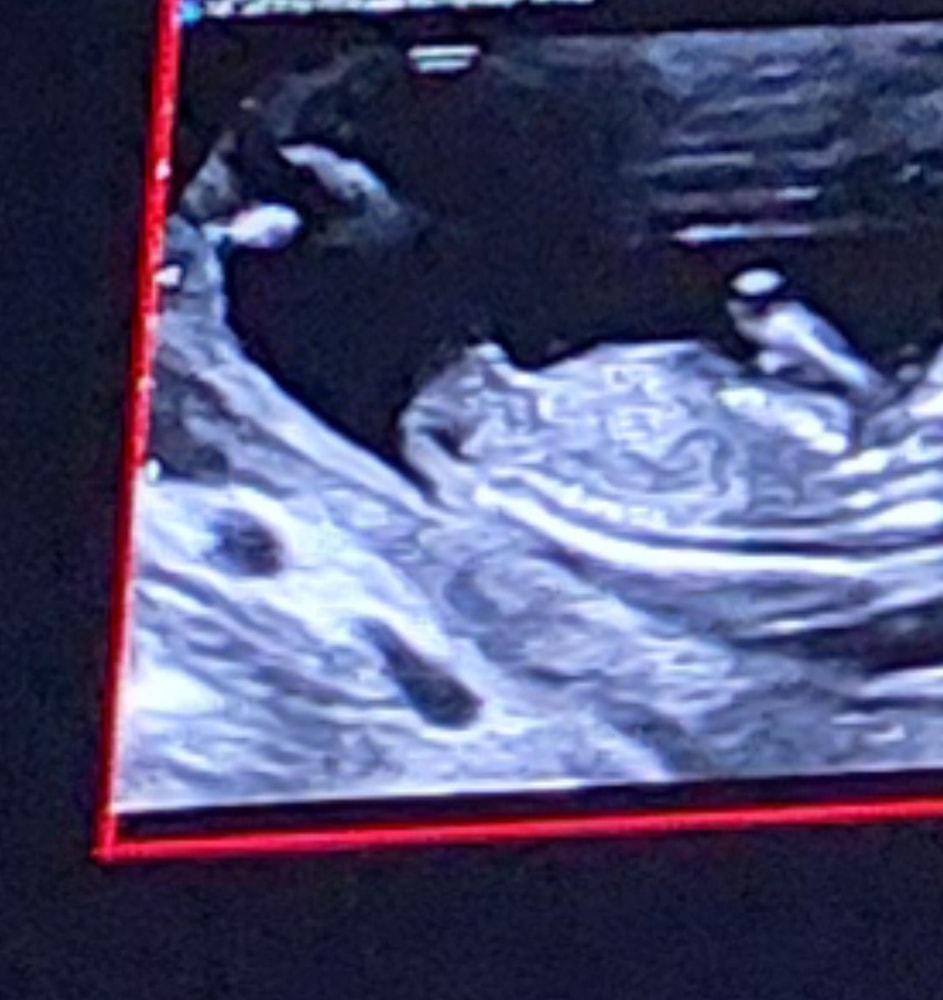

Полина , вот я тоже думала,что это нога))фоткала с экрана,там стопкадры были,вот такое есть ещё